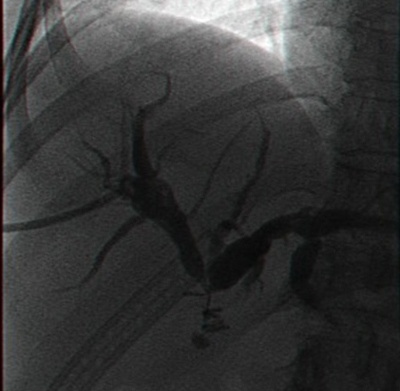

לאחר פתיחת הבטן ובדיקת איברי הבטן ניגשים לכריתת כיס המרה. תחילה מזהים את צינור כיס המרה ואת הכולדוכוס, מזהים את עורק כיס המרה וקושרים אותו בסמוך לכיס המרה. לאחר מכן קושרים את צינור כיס המרה קרוב לכיס המרה, בשלב זה במידת הצורך (ראה הוריות בדרכי מרה) פותחים אותו ומכניסים לתוכו צינורית, שדרכה מצלמים את דרכי המרה (תצלום .21.8). בצילום זה יש לשים לב:

- לאנטומיה של דרכי המרה.

- לליקויים בתוך דרכי המרה, שעלולים להתאים לאבנים או לשאתות בדרכי המרה.

- למעבר חופשי לתריסריון.

- לרוחב הכולדוכוס.

- לרוחב העץ הביליארי התוך-כבדי ולהדגמתו.

בעבר נהגו לבצע צילום דרכי מרה (כולאנגיוגרפיה) תוך-ניתוחית בכל החולים שנכרת בהם כיס מרה. הכולאנגיוגרפיה הקטינה את מספר הפתיחות של דרכי המרה מ- 41% מסיבות קליניות ל- 25% מהחולים, וכמו-כן נתגלו כ- 4% מהלוקים באבנים בדרכי המרה בלא כל תסמינים אחרים. במשך השנים, עם התפתחות ה- EUS וה- ERCP, המאפשר זיהוי אבנים, הן לפני הניתוח והן לאחריו וטיפול בהן, ההוריות לצילום תוך-ניתוחי של דרכי המרה הצטמצמו ביותר וכוללים חולים בהם ה- ERCP לא הצליח טכנית, או שנתגלה פגם בדרכי המרה שלא טופל לפני הניתוח, חולים תסמיניים כגון חולי צהבת, חולים הלוקים בכולדוכוס מורחב של יותר מ- 16 מ"מ, במקרים שבהם האנטומיה בניתוח אינה ברורה. כולאנגיוגרפיה באותן הוריות ניתן לבצע גם בחולים המנותחים בשיטה לפרוסקופית.